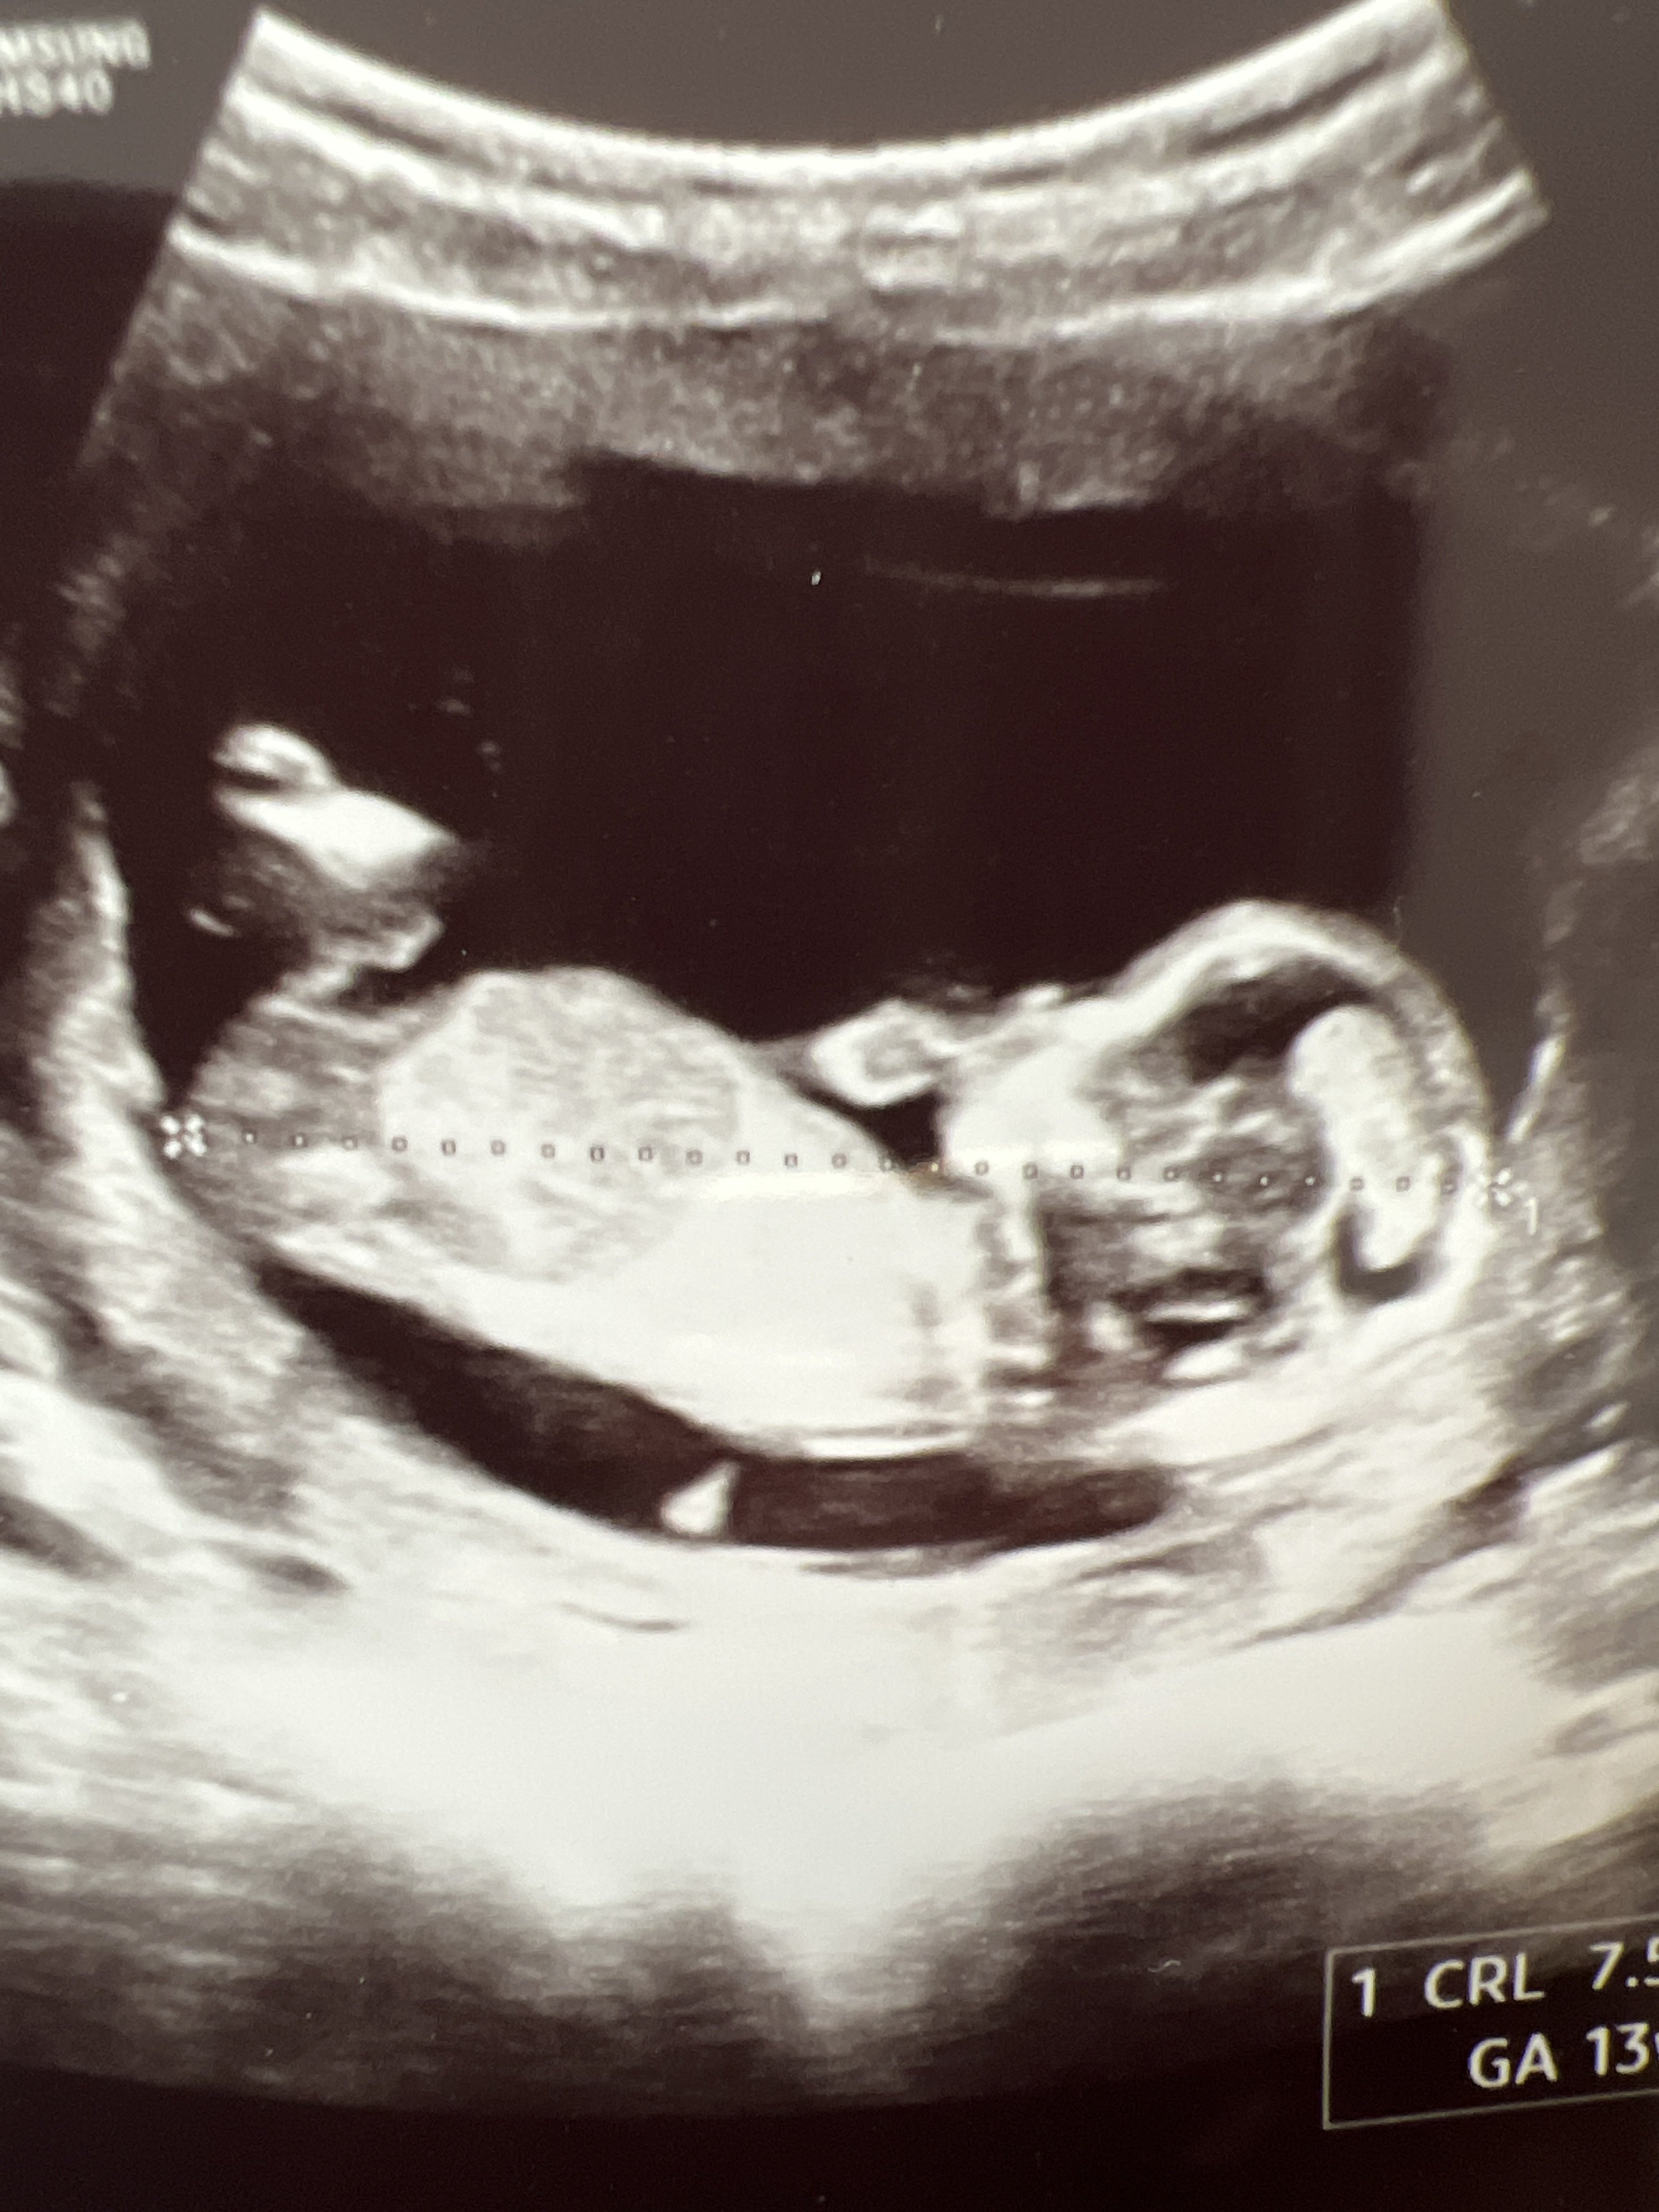

A lekarz określił płeć, że dziewczynka? Bo mi się wydaje, że chlopczykWitam mam zdjęcie z 13,5tygodnia

A drugie z 17 czy może to być przerośnięta łechtaczka? Pozdrawiam

Witam mam zdjęcie z 13,5tygodnia

Dla mnie na zdjęciu nocnikowym ewidentnie widać mosznę z której będą jądra